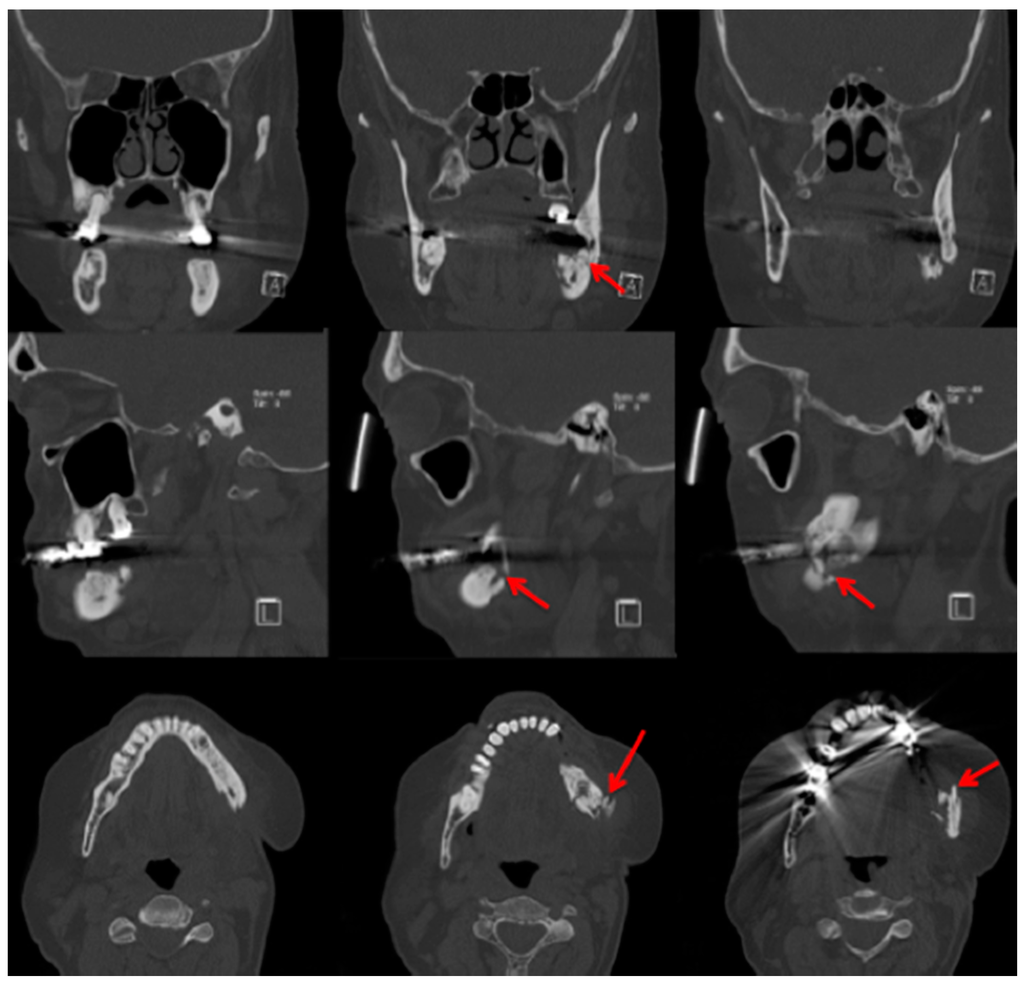

2.3. Computed Tomography

Bianchi et al. [20] assessed 32 panoramic radiographs and CT scans in detail for the following features: “structural alteration of trabecular bone, from initial change in thickness and mineral content of the trabeculae to the formation of microlacunae; cortical bone erosion; osteosclerosis; small (less than 15 mm) sequestrum; extensive (more than 15 mm) sequestrum; and presence of periosteal new bone.” They found that CT was superior to dental panoramic radiographs in detecting all the radiologic signs [20]. Cortical bone erosion and trabecular bone resorption were visible to different extents. In their readings they found that panoramic radiographs missed the correct diagnosis of sequestra in 15 cases [20]. In our example case, even a fracture could be missed if only the panoramic radiograph is assessed (Figure 3 and Figure 5).

Figure 5.

Computed tomography (Siemens, Sensation 64) Patient: 66 years old, male, secondary osteoporosis due to castration, alendronate. Red arrow points in the direction of the fracture due to the bisphosphonate necrosis. The panoramic radiograph is shown in Figure 3 and the 99Tcm-DPD SPECT and 99Tcm-DPD SPECT/CT in Figure 8 and Figure 9 respectively. AAMOS staging: stage 3.

The extended follow-up (CT scans at 3, 6, 12, 18, and 24 months) by Bedogni et al. was able to show that “CT signs of recurrent disease are apparent within 6 months after surgery and precede clinical manifestations of BRONJ” [21]. Sanna et al. stated that CT helps to differentiate between MRONJ and metastasis [33]. Elad et al. assessed 110 CT scans and stated “the mandibular canal cortex was resistant to the destructive process of the jaw, unlike in metastases” [34], but there are MRONJ cases which are still difficult to diagnose even with CT. Clinical examination is mandatory for diagnosis [35]. Farias et al. mentioned that the CT image features did not differ significantly between cases with or without exposed bone [35]. Not only are changes in bone investigated in patients with MRONJ, but thickening of the sinus maxillary mucosa is also examined [20]. A study by Gallego et al. were able to show patients with MRONJ had greater probability of presenting sinus mucosal thickening in comparison to a healthy group. They used a thickening of >3 mm as their measurement value. In their assessment, they found that the thickening was present more in patients with “advanced-stage disease” [36]. In their study, Hutchinson et al. concentrated on radiographic characteristics in patients with “stage 0 disease” [37]. Ten patients met the criteria for “stage 0”. They included 1× panoramic image, 2× CBCT scans, and 9 CT scans. The authors reported “Diffuse osteosclerosis in clinically symptomatic areas, characterised most with extension beyond the involved site, density confluence of cortical and cancellous bone, prominence of the inferior alveolar nerve canal, markedly thickened and sclerotic lamina dura, uniform periradicular radiolucencies, cortical disruption, lack of bone fill after extraction, and a persisting alveolar socket.” [37]. Hamada et al. [38] reported “A simple evaluation method for early detection of bisphosphonate-related osteonecrosis of the mandible using computed tomography”. They found no significant differences between means of administration (intravenous or oral) and length in regard to “cancellous bone CT radiodensity value, cortical bone CT radiodensity value, and cortical bone width.” [38]. Otherwise they found differences between the MRONJ group and a control group regarding cortical bone width. In cancellous bone, CT radiodensity values even varied “among the BRONJ area, the non-BRONJ area, and the control groups” [38]. A limitation of this study, which should be mentioned, was the size of the MRONJ group. A total of 20 patients were included; only 4 patients received bisphosphonates orally. Of these 4 patients, 3 patients received risedronate and 1 patient received alendronate [38], therefore although it provides some valuable information, a larger sample size would be desirable. The patient group assessed in the article by Wutzl et al. included 17 patients. All of them presented sclerotic zones. In 9 of these patients MRI and scintigraphy were performed. They stated that, “sclerotic changes on the CT scan appeared hypointense on MRI.” [39]. Bisdas et al. found “sclerotic regions in the jaws with or without periosteal bone proliferation.” [40]. A large multicentre study (“MISSION”) assessed in detail 799 patients suffering from MRONJ in regard to staging/CT. From their point of view, future staging systems should consider both clinical signs and CT findings [41].